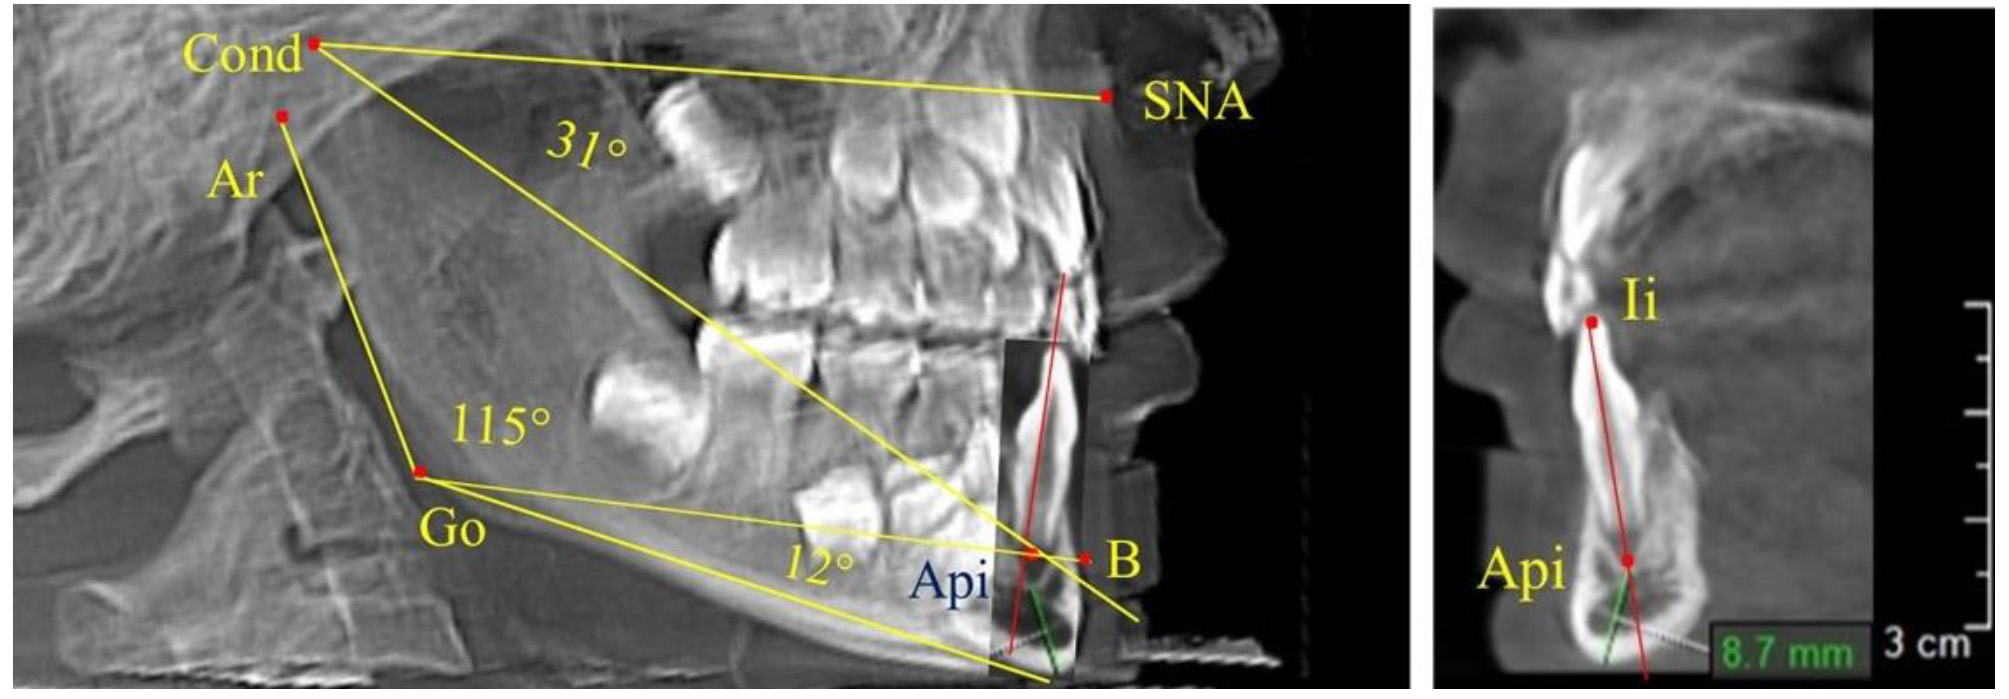

Особенность анализа телерентгенограммы в периоде сменного прикуса заключалась в том, что наслоение зачатков постоянных зубов затрудняло определение апикальной точки нижнего резца. В подобных случаях использовали метод совмещенного анализа телерентгенограммы с фрагментом томограммы, на котором, также как и на телерентгенограмме, определяли положение резцовой и апикальной точек с построением условной вертикали, которая служила ориентиром для совмещения фрагментов (рис. 2).

Рис. 2. Особенности совмещения телерентгенограммы с фрагментом томограммы в сменном прикусе

Данная методика позволяла устранить некоторые неточности ТРГ, связанные с наложением на объект исследования рядом расположенных рентгеноконтрастных структур. Данная методика может быть использована при определении положения апикальной точки медиального нижнего резца в ходе исследования гнатического отдела лица.